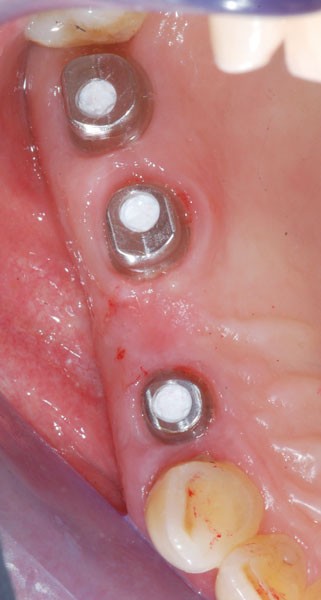

Au maxillaire, 3 implants Astra Tech Implant EV (Dentsply) sont posés en un temps chirurgical. Une empreinte pick-up sera réalisée après 4 mois de cicatrisation.